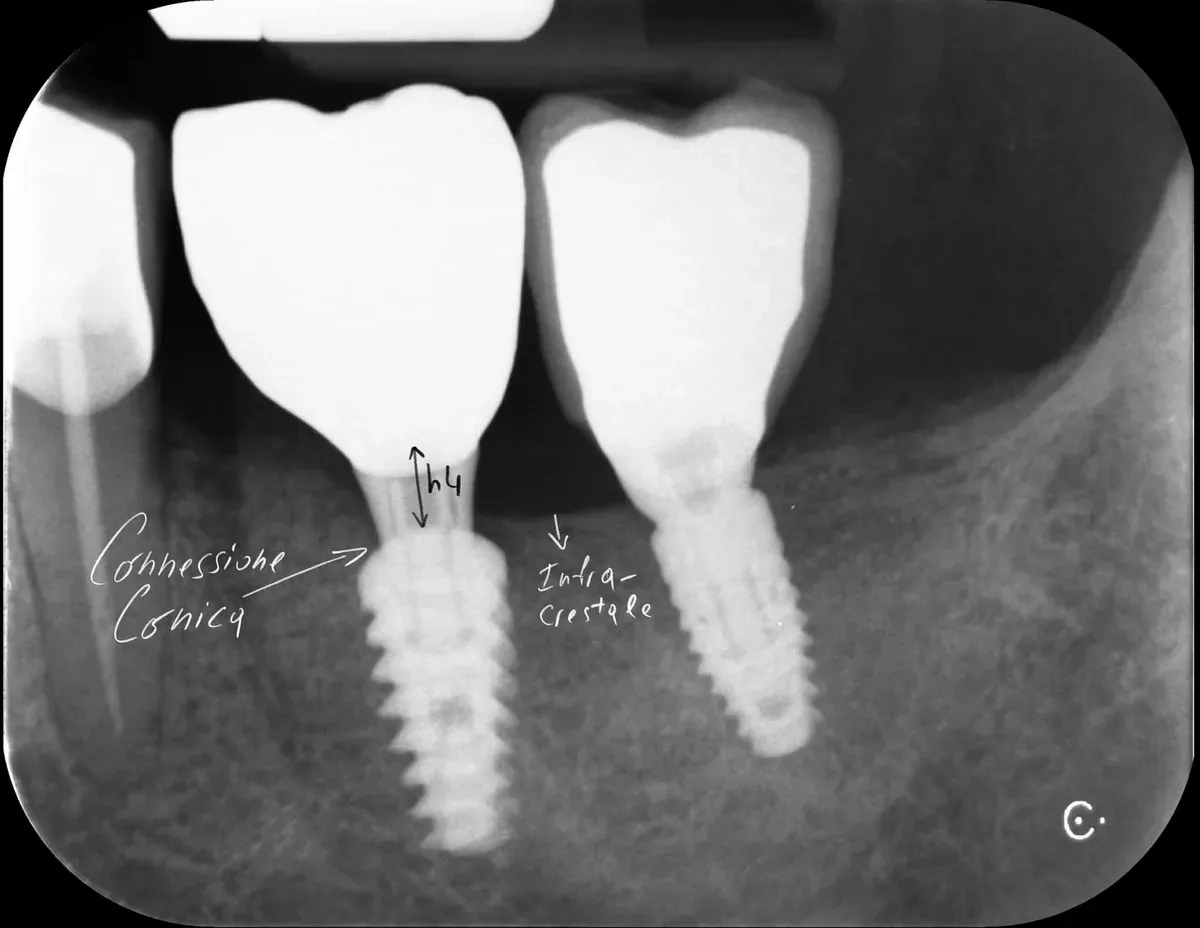

Connessione interna, esterna e conica: studi recenti

Due network meta-analisi recenti hanno rafforzato il concetto. Camps-Font e collaboratori hanno dimostrato che le connessioni coniche interne producono significativamente meno perdita ossea marginale rispetto alle esterne o alle interne piatte a 12 mesi dal carico protesico, con meno complicazioni protesiche (https://doi.org/10.1016/j.prosdent.2021.09.029). Le statistiche sulla sopravvivenza e le complicanze biologiche, invece, erano sovrapponibili.

Ma la direzione dell’evidenza è chiara: le connessioni coniche interne, specialmente con platform switching intrinseco, offrono un ambiente biologico più favorevole (vedi anche Connessione Conica vs Flat 5-0).

In pratica: se usate bone level, la connessione conica interna è preferibile. Se usate connessioni esterne o flat interne, sappiate che state partendo in svantaggio biologico e dovete sempre prendere in considerazione il limite biologico del posizionamento verticale dell’impianto.

Platform switching: un’idea ottima

Il platform switching — l’uso di un abutment di diametro inferiore rispetto alla piattaforma implantare — ha basi biologiche solide. L’effetto è triplice. Il concetto è stato pubblicato da Lazzara e Porter nel 2006 (https://pubmed.ncbi.nlm.nih.gov/16515092/).

Primo: lo spostamento laterale della giunzione impianto-abutment allontana l’infiltrato infiammatorio dall’osso marginale . Secondo: le fibre collagene attorno agli abutment con platform switching si organizzano in modo circolare, stabilizzando il connettivo e proteggendo l’osso sottostante — come dimostrato istologicamente da Rodríguez e collaboratori su impianti conici nell’uomo (https://doi.org/10.11607/prd.2580) Terzo: la concentrazione dello stress meccanico si sposta dall’osso cervicale verso l’impianto stesso, anche se con un potenziale aumento dello stress sulla vite (https://doi.org/10.1111/j.1600-0501.2007.01398.x).

Sul piano clinico, Duque e colleghi hanno riportato una prevalenza di peri-implantite del 6,6% per impianti con platform switching contro il 15,6% per impianti convenzionali (https://doi.org/10.1590/1807-3107bor-2016.vol30.0005). Le revisioni sistematiche confermano una maggiore stabilità dell’osso crestale attorno agli impianti platform-switched (vedi per esempio (https://doi.org/10.1111/clr.12339).